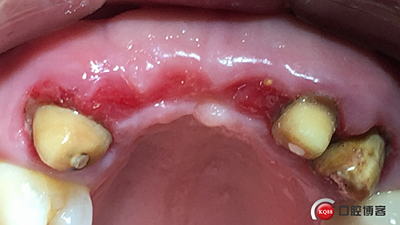

患者女性,52歲,缺失三顆牙,骨性前突,頜弓窄,身高175,魁梧,放了三顆牙是不是有點(diǎn)細(xì)?左上3開膠了,牙體有腐蝕。

設(shè)計(jì):1.僅做牙槽嵴頂水平切口,不做垂直切口,2.缺牙區(qū)由三顆牙改成兩顆牙,3.鄰牙冠延長(zhǎng)。